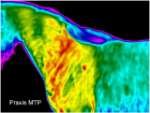

Wirbelblockaden können mit der thermografischen Diagnostik sichtbar dargestellt werden. Blockierte Wirbel werden behandelt und anschließend mit der Matrix-Rhythmus-Therapie weiter therapiert.

Wirbelblockaden sichtbar dargestellt mit Thermografie Diagnostik

Durch eine bestehende Blockade im linken HWS - Bereich, wurde die rechte Halsseite muskulär überstrapaziert. Folglich entstanden Folgeprobleme mit Einschränkung in diesem Segment. Mit Hilfe der Thermographie kann das Ausmaß einer Entzündung im Verlauf des Muskela beurteilt werden. Folglich entstanden dadurch Blockaden. Eineosteopathische Untersuchung erfolgte, zur weiteren Behandlung wurde dieMatrix-Rhythmus-Therapie eingesetzt.

Damit sich die Weichteilstrukturen an die neue Funktion gewöhnen konnten um die neue Funktion wieder aufrecht zu erhalten. Ansonsten würde der Körper wieder in seine alte Funktionsstörung zurück fallen und die Störungen treten erneut wieder auf.